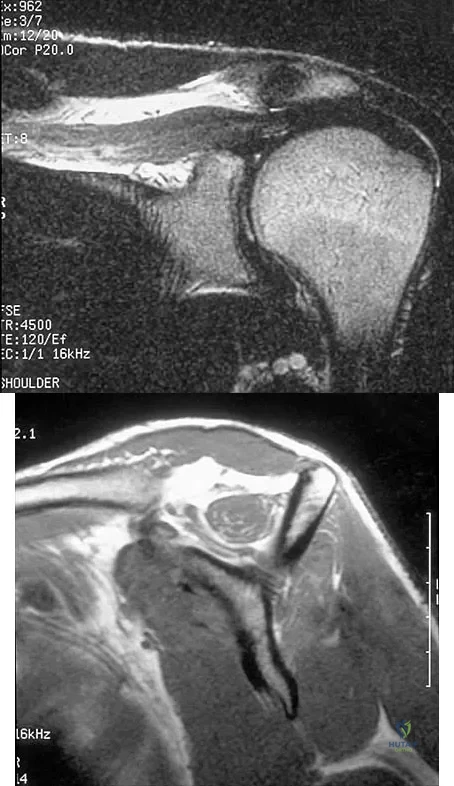

A patient has right shoulder pain. Figure 1a shows a gadolinium-enhanced transverse MRI scan at the level of the coracoid. Figure 1b shows an arthroscopic view of the anterior structures from a posterior portal. These images reveal which of the following findings?

A 39-year-old man has anterior shoulder pain after landing on his abducted left shoulder while playing softball. Examination reveals a stable glenohumeral joint, pain on passive external rotation of greater than 25 degrees, and pain and weakness on belly press (Napoleon's) test. An MRI scan is shown in Figure 32. To provide maximum pain relief and return of function, management should include